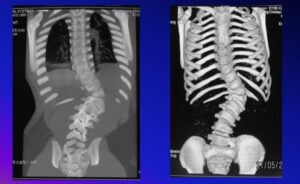

- Radiographic and special studies such as CT, MRI and Ultrasound

Posterior Vertebral Column Resection is indicated for:

- Complex multiplanar deformity

- Previously fused spine

Patients with Poor Pulmonary function